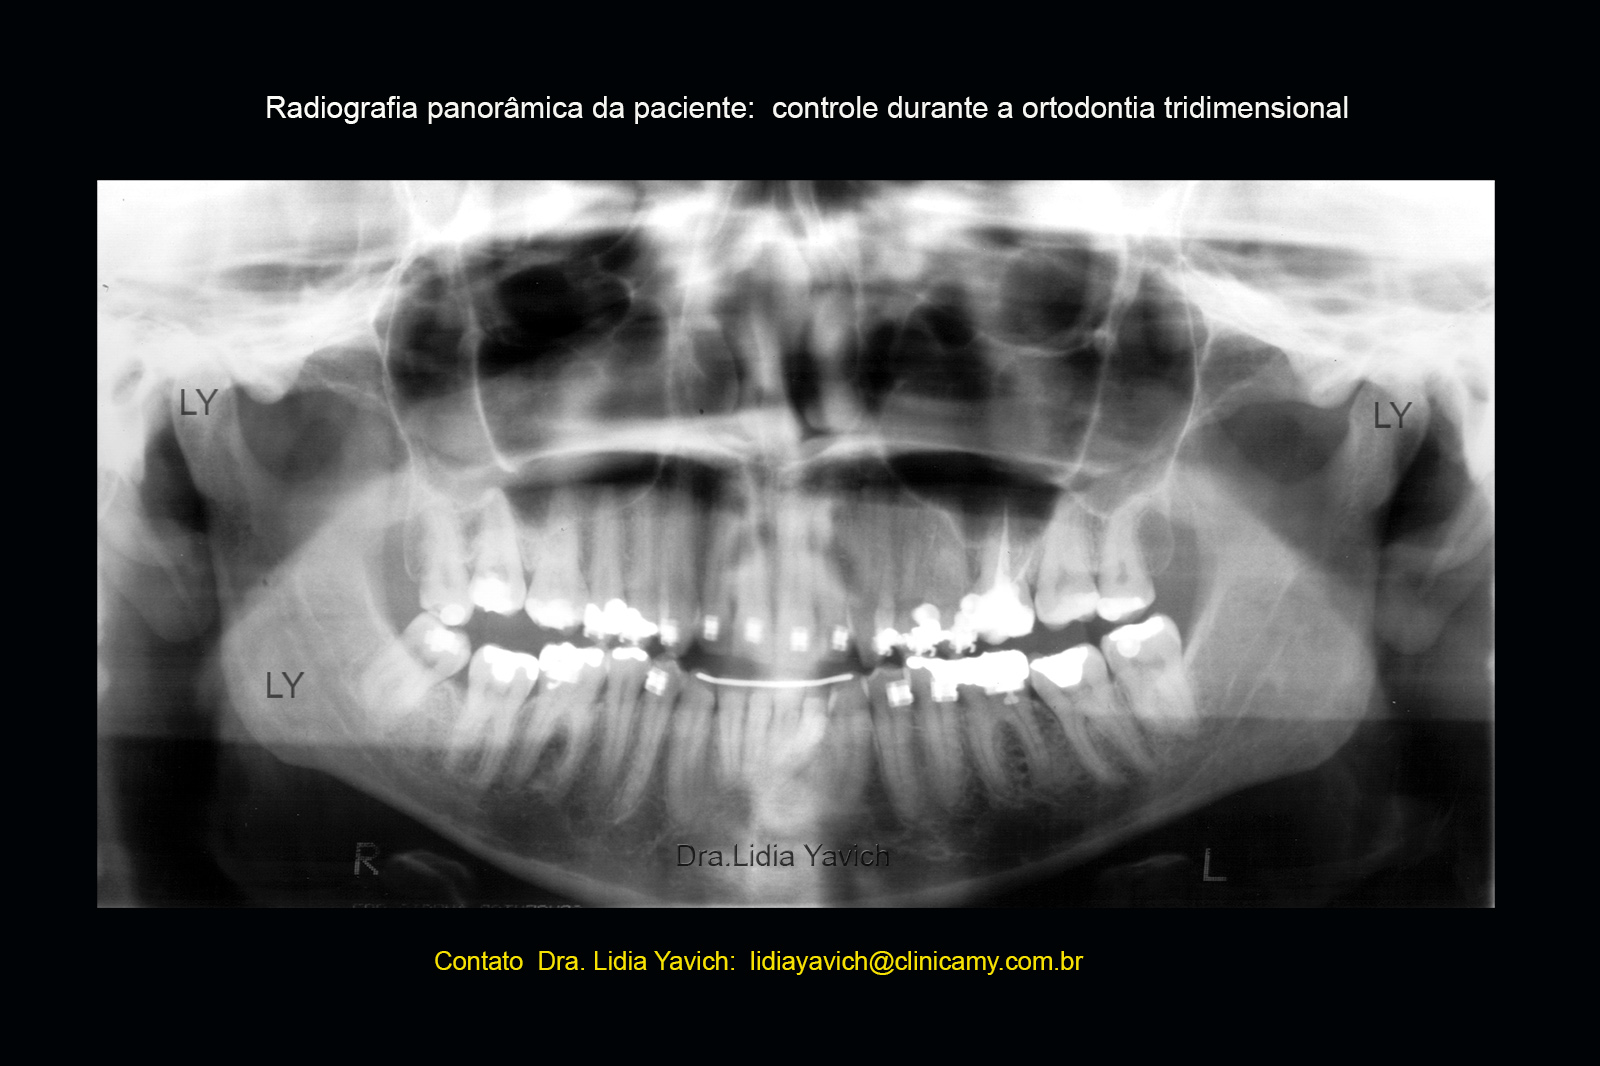

Neste momento se inicia uma ortodontia tridimensional para a retirada do DIO.

Esta Ortodontia como já foi explicado em publicações anteriores (ver a publicação Ortodontia Tridimensional na Segunda Fase dos Tratamentos das patologias da Articulação Temporomandibular), deve manter sempre a localização mandibular em equilíbrio com os planos musculares, articulação temporomandibular e planos dentários conseguidos na primeira fase do tratamento.

Para isso temos ferramentas como a eletromiografia de superfície e a desprogramação mandibular que nos ajudam a controlar o funcionamento do sistema.

Serão mostradas poucas sequencias ate a retirada total do DIO (dispositivo intraoral)

Erupção ativa dos segmentos laterais, já em uma etapa mais avançada. Os dentes estão preenchendo o espaço antes ocupado pelo DIO.

Radiografia panorâmica de controle da erupção ativa. Corresponde a sequencia mostrada na imagem anterior.